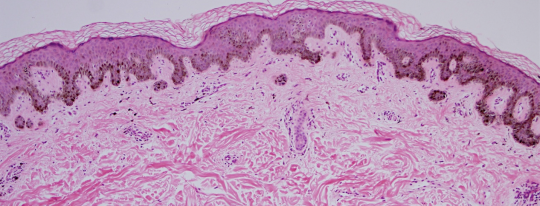

VA40: Right Upper Arm, Compound Melanocytic Nevus, Clarks

VA40: Right Upper Arm, Adjacent, Normal